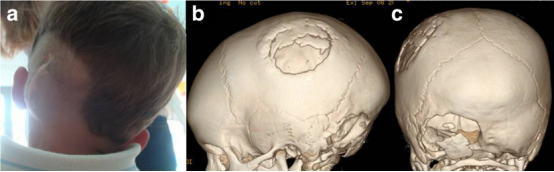

关于前一种技术(自体骨移植),板障间隙的发育(通常在4 岁左右完成)长期以来被认为是在幼儿中应用该技术的主要限制。然而,随着现代器械如压电手术刀的应用,目前已可将骨瓣分割至薄至 3 毫米(图 2)。尽管该技术能够利用存活骨修复颅骨缺损,但由此获得的骨瓣厚度较薄,可能会放大影响骨瓣吸收的相关因素(如患者年龄、骨缺损的特定创伤病因等),最终导致骨整合失败(图 3)。

图 3:右侧枕下区缺损,采用同侧顶骨分割取下的自体移植骨修复(a),但因供区骨瓣次全吸收(b)以及枕下区假性脑脊液瘤形成导致移植骨吸收和移位而出现并发症(c)。